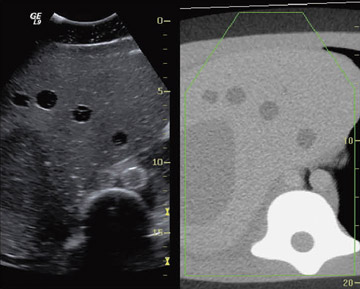

Volume Navigationのいくつかの応用例を示す。図5はCTで検出され,超音波では明瞭に描出されない病変をVolume Navigationを用いて,CT画像を参照しながら超音波断層上で腫瘍の位置を再確認し,超音波ガイド下穿刺を行っている例である。

図5 腹部消化器領域での適用例